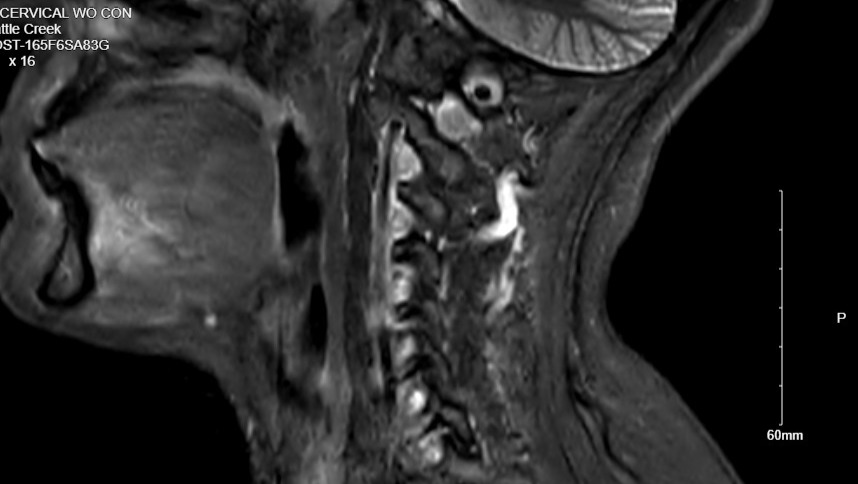

For over a year, I've had a pain in my neck and right shoulder blade. I thought I pulled something. Fast forward to May of this year. X-rays showed a narrowing of my cervical spine. I was sent to physical therapy. After 8 weeks of no relief, the PT recommended I have a follow-up appointment with my primary provider. Then they ordered an MRI. The results showed nerve damage caused by the degeneration of my C6-C7. I was then referred to a neurosurgeon at Bronson Methodist. The neurosurgeon recommended a fusion surgery that will most definitely help me. My surgery is scheduled for October 7.